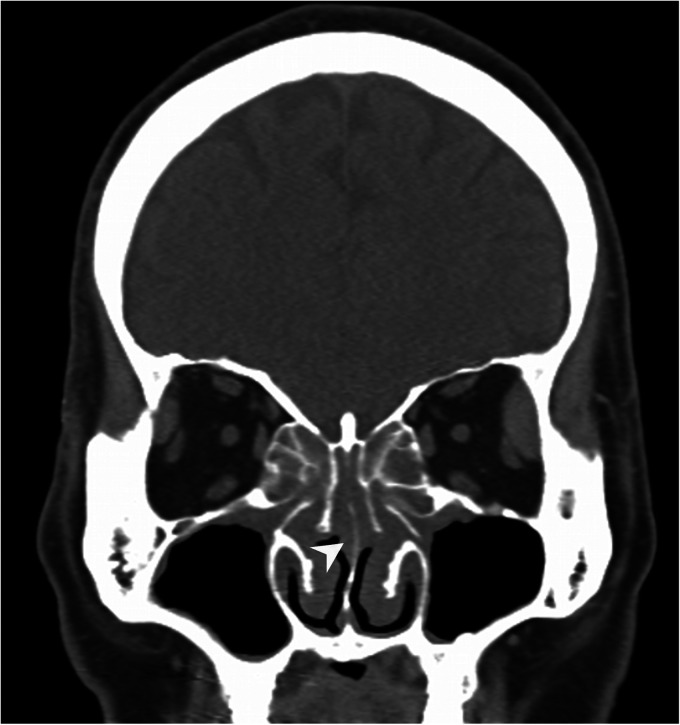

Conclusion: Our findings indicate that CCAD is significantly associated with olfactory dysfunction and that FESS can effectively improve olfactory function. To optimize postoperative olfactory outcomes, precise removal of polyps from the olfactory cleft without damaging the neuroepithelium is recommended. Our study provides valuable insights into the management of CCAD patients undergoing FESS and can guide surgical decision-making to achieve optimal olfactory function outcomes.

Abstract Image